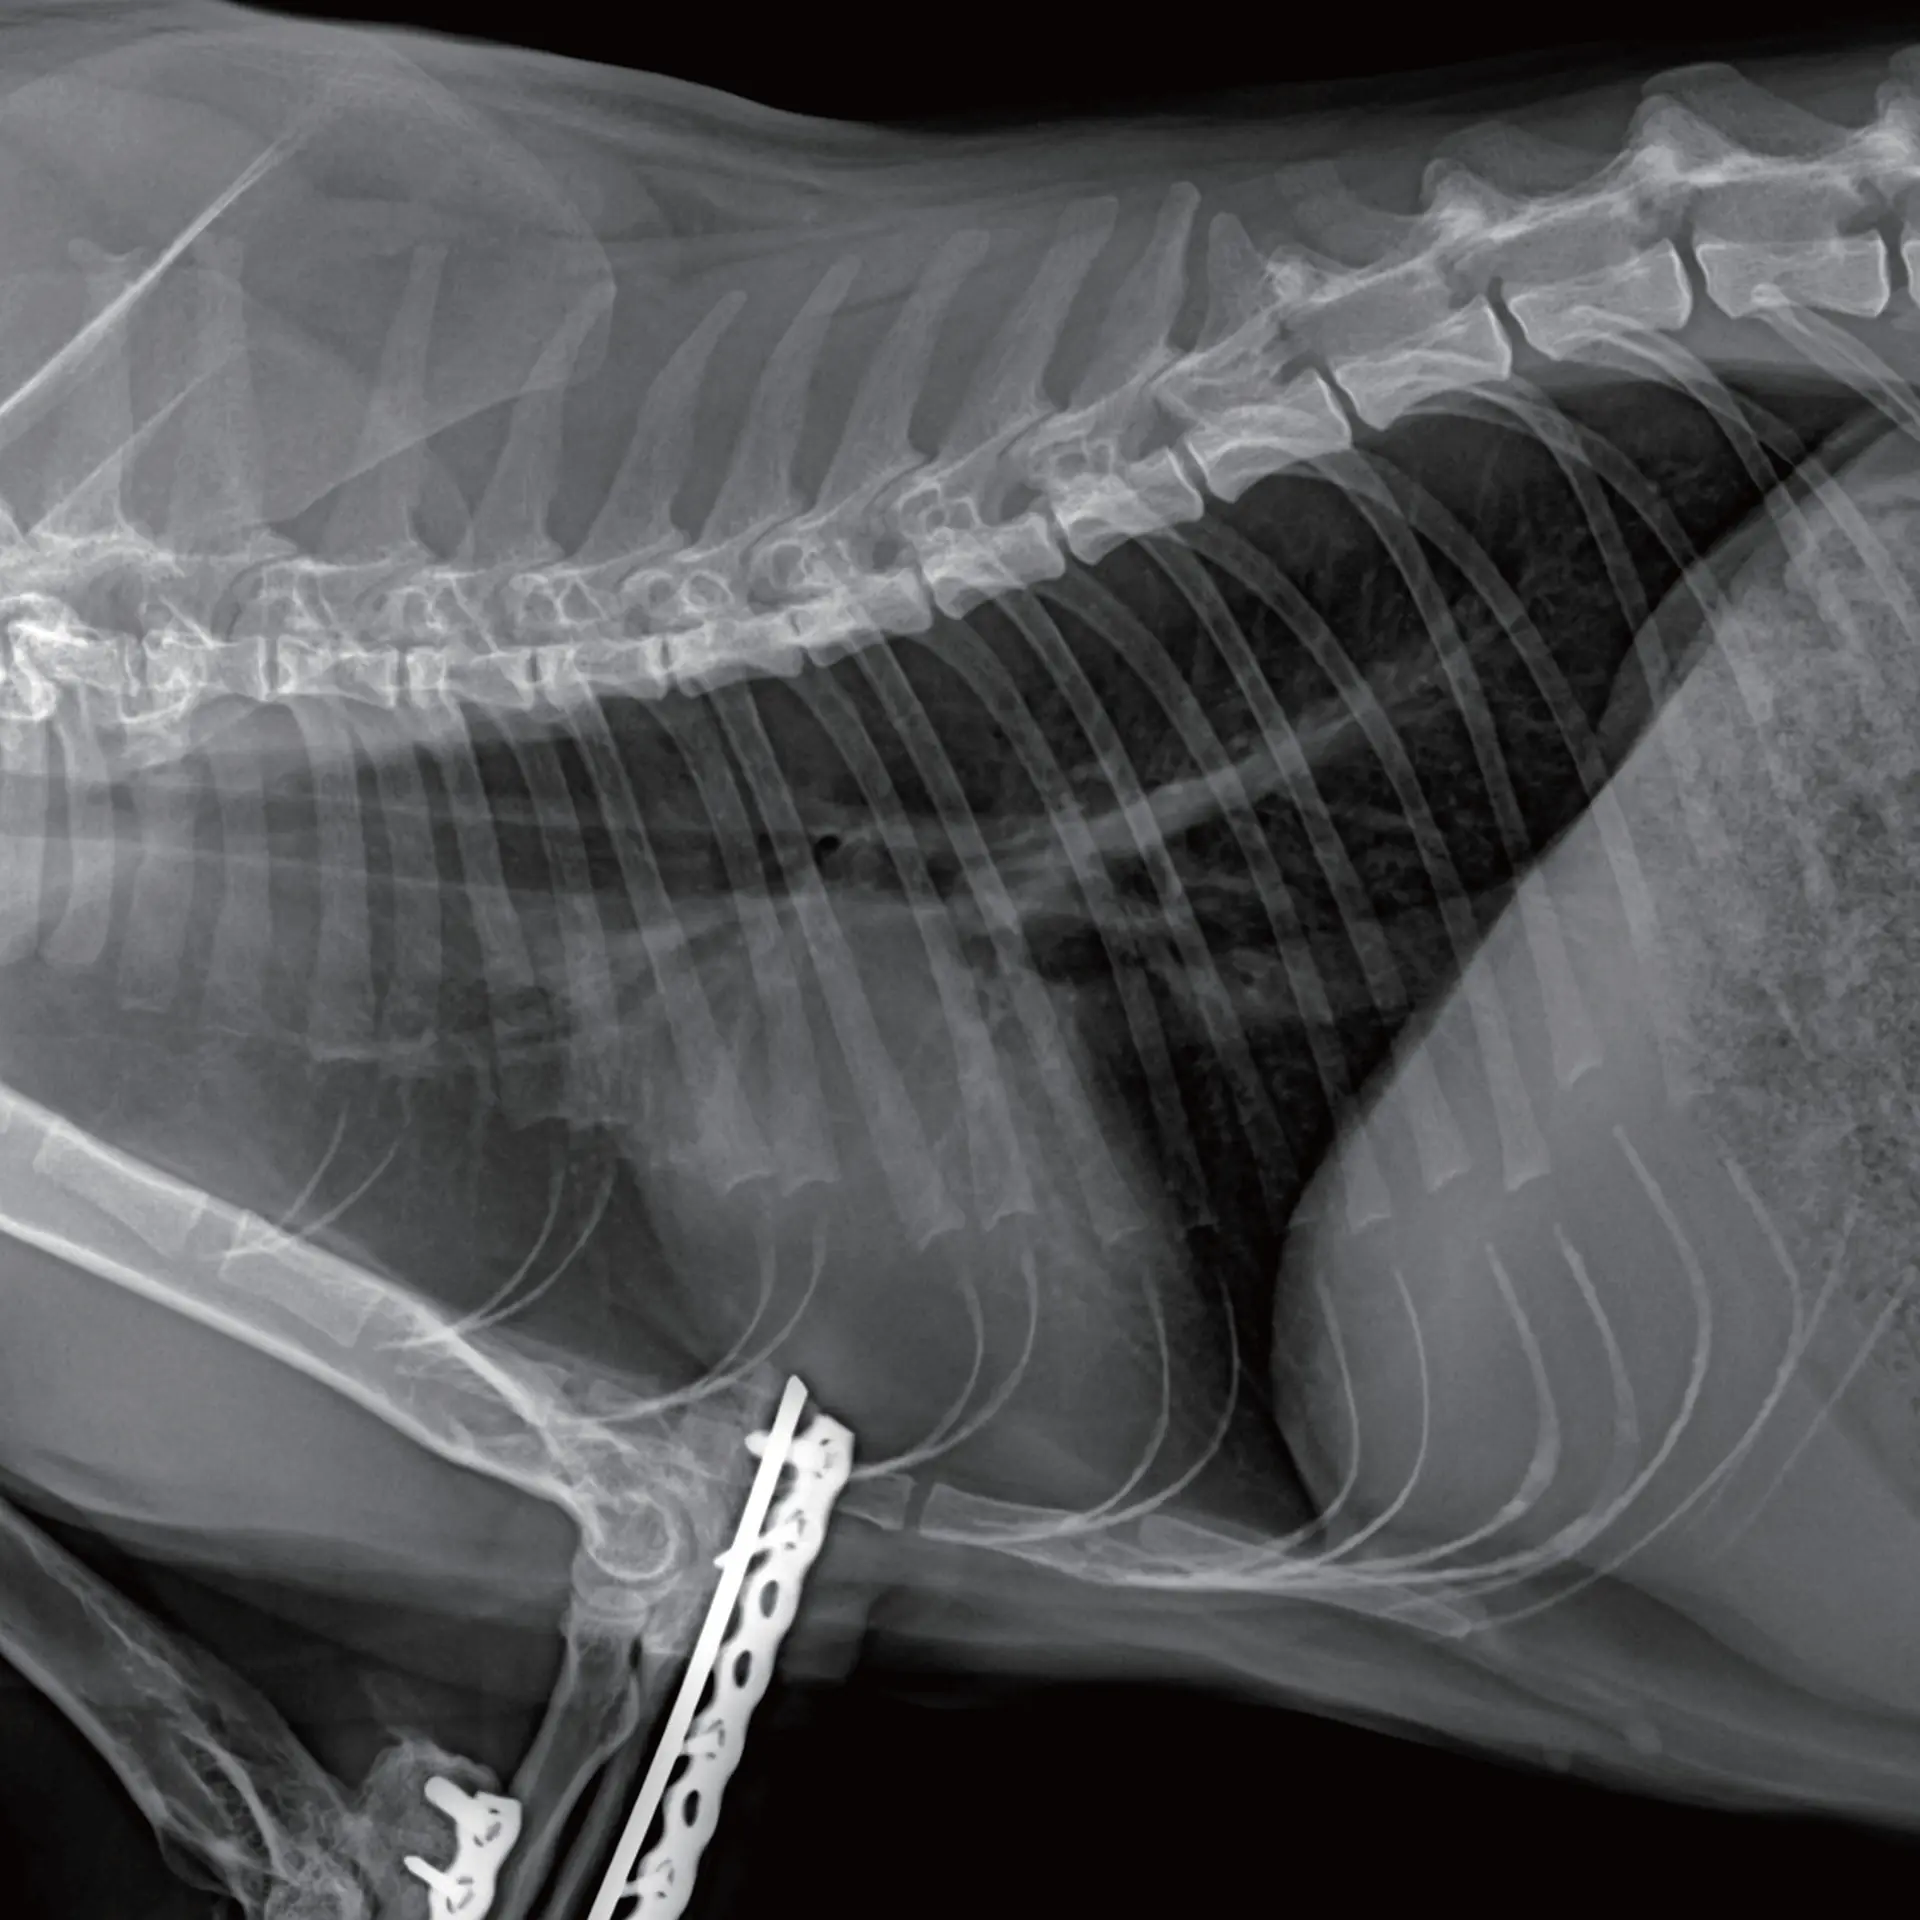

Akciğer Görüntüleme

Ortopedik Görüntüleme

Kırık sonrası post-operatif inceleme